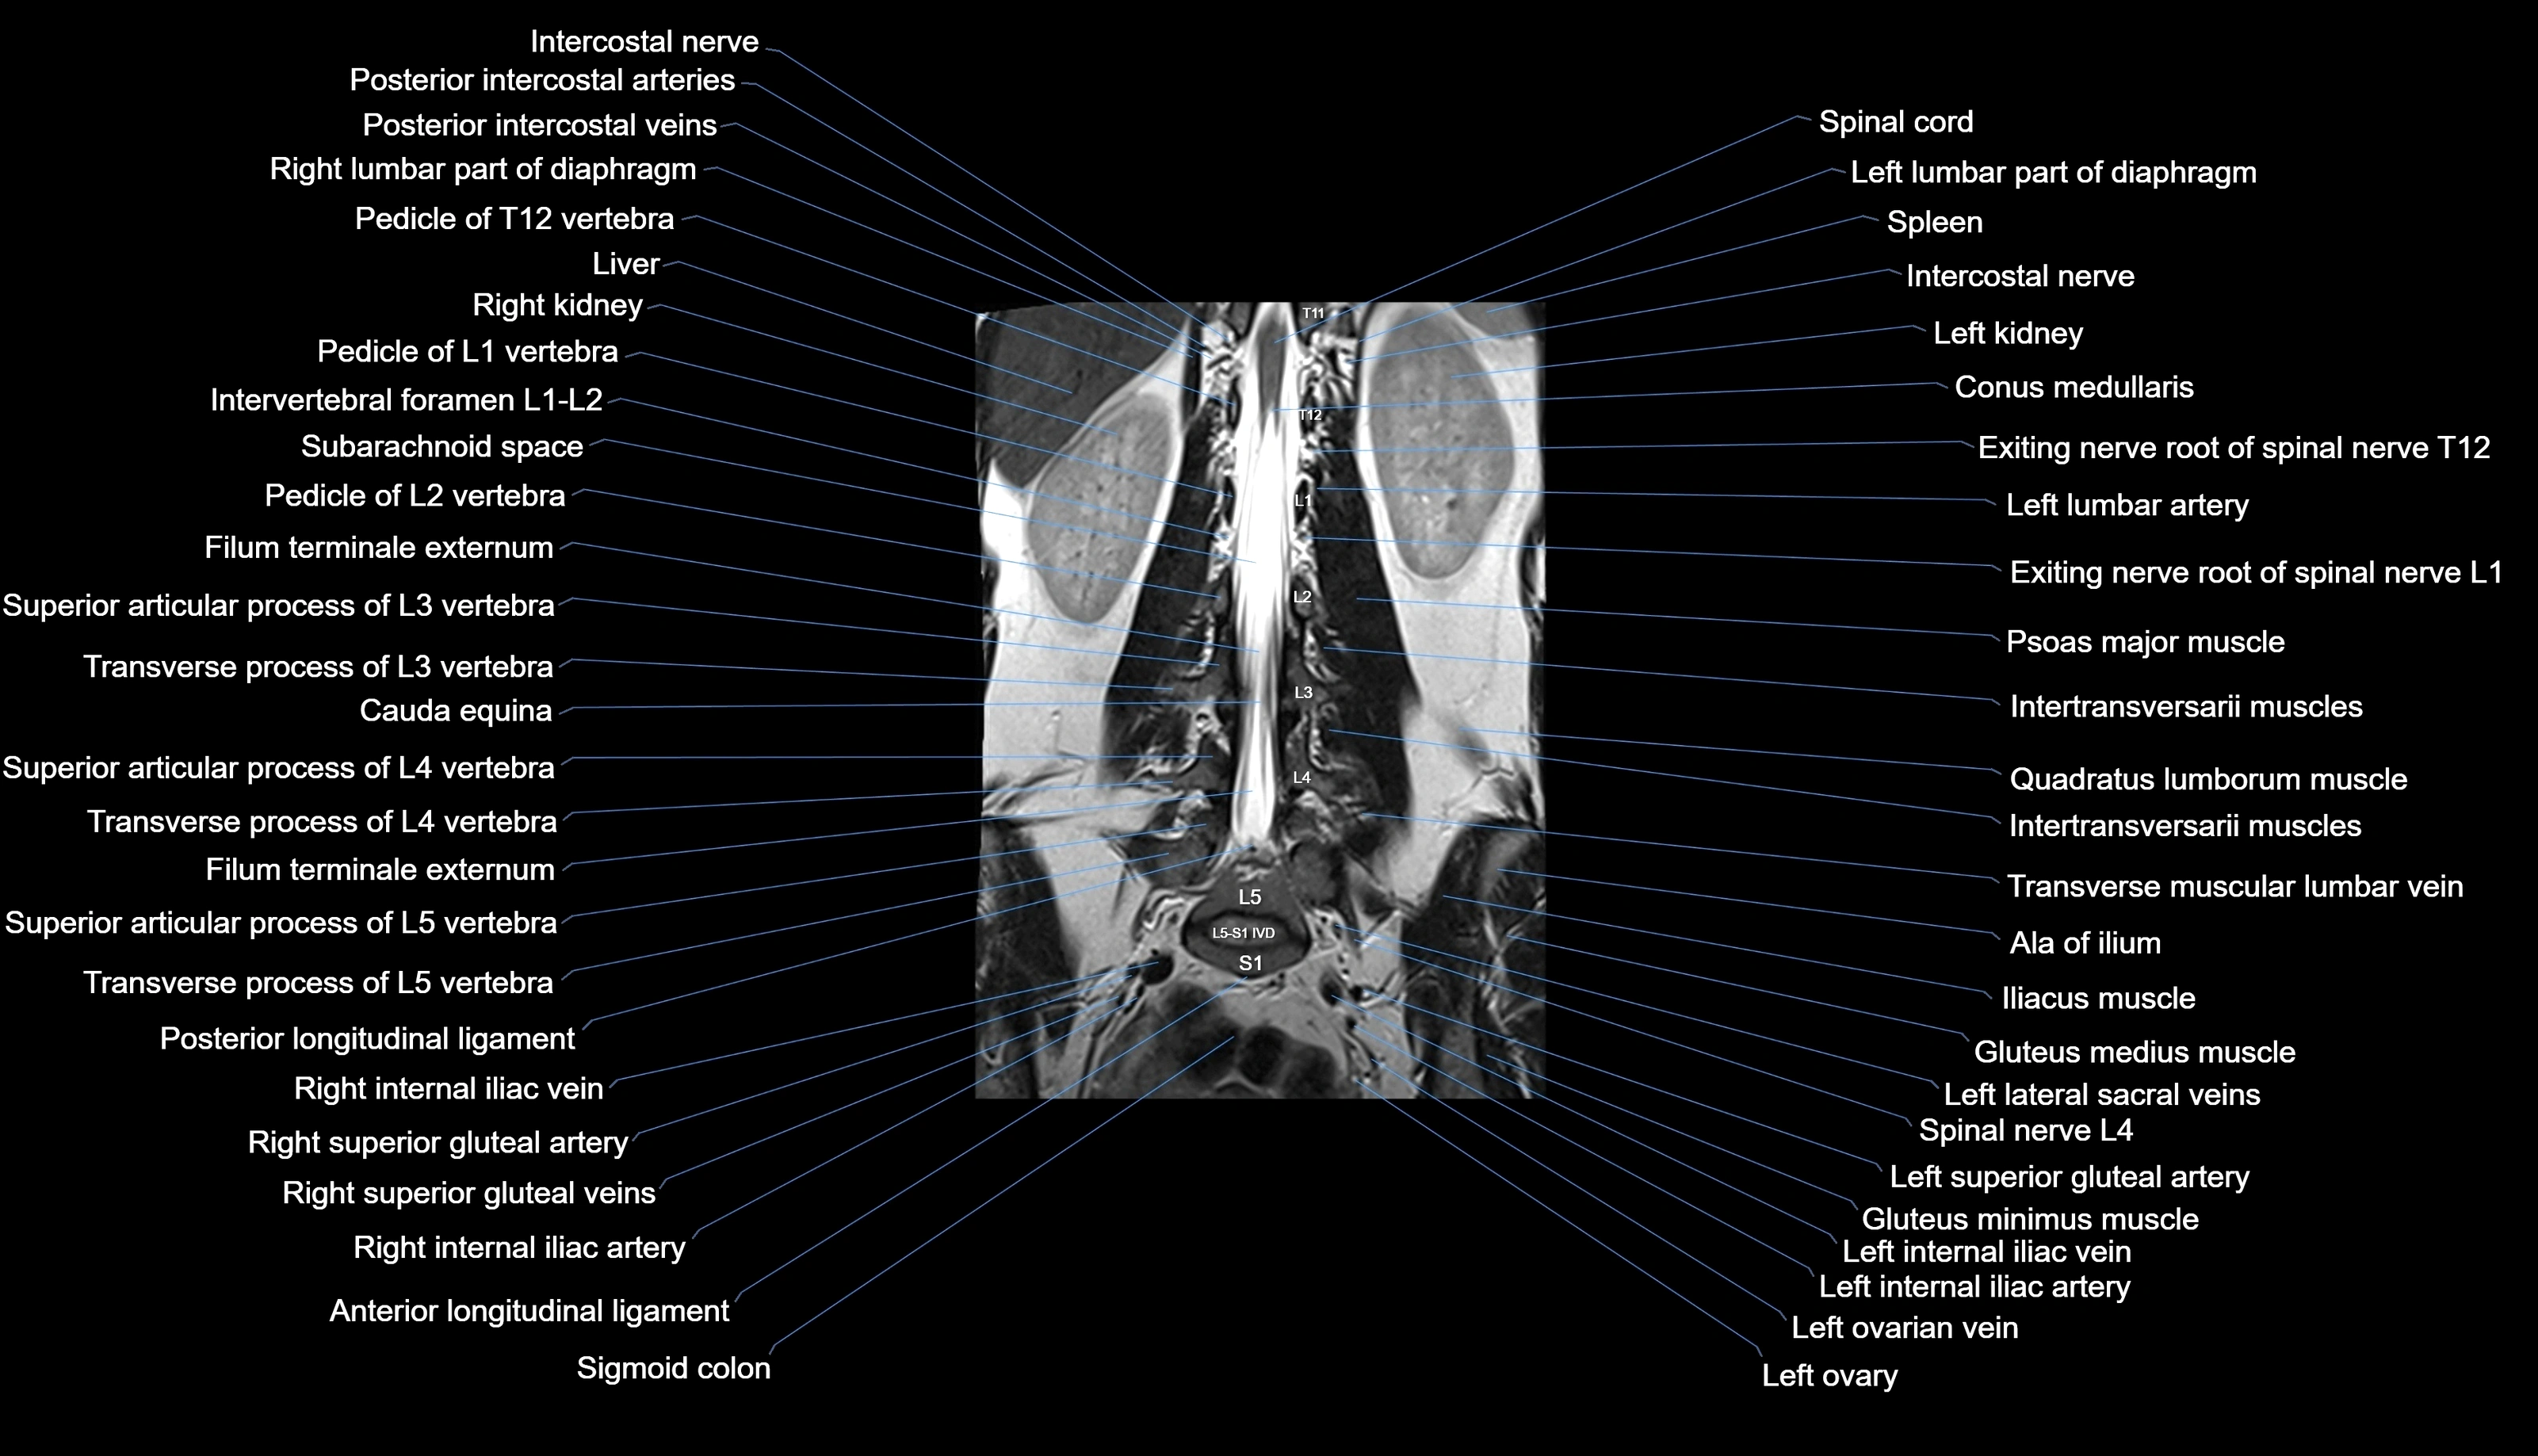

MRI images